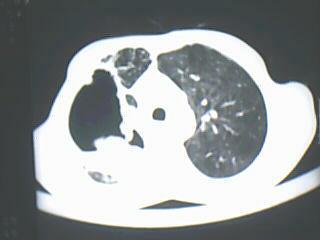

以下是引用深泽交通医院在2009-8-7 12:20:00的发言:[br]肺结核;肺囊肿合并真菌球寄生

以下是引用随光逐影在2009-8-7 15:40:00的发言:[br]考虑右肺继发性肺结核并右肺上叶空洞形成,两肺支气管播散;不排除右肺上叶空洞内霉菌感染可能。

以下是引用jiangjing在2009-8-7 14:38:00的发言:[br]右上肺张力空洞,酐珞坏死灶,支气管扩张,多发播散灶,纵膈淋巴结显示,胸膜增厚---结核